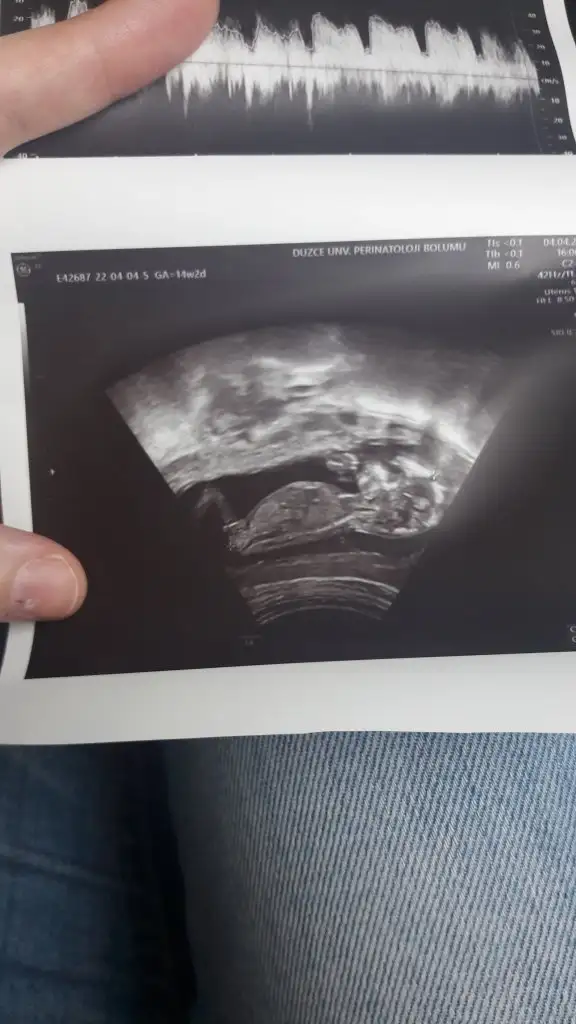

Canım sana öncesinde erkek mi demislerdikızlae bu fotodan erkeğe benzeten varmı hiç doktor %90 kız dedi hevesim var bişler almaya ama değişebilirmiki?

Doktorun iyi uzman bir doktorsa doğrudur.benimkini bildi 11,5 haftalikken bacak arasini gormeden yandan bakarak.kızlae bu fotodan erkeğe benzeten varmı hiç doktor %90 kız dedi hevesim var bişler almaya ama değişebilirmiki?

baya erken bilmiş doktorum üniversitede doçent yorumları iyi bi tanıdığımda gitmişti buna erkeğe benziyo dedi ilk erkekde çıktı inşallah bunuda foğru bilmiştirDoktorun iyi uzman bir doktorsa doğrudur.benimkini bildi 11,5 haftalikken bacak arasini gormeden yandan bakarak.

Belli oldu mu cnm cinsiyetinizKıza benziyo dedi hala karnım bile çıkmadı yiyememekten bende koku tiksinme bulantı kusma hepsi var güzel bişeyde yesem ağzımda leş gibi bi tat var geçmiyo bide midem bulanmazken doymuyorum ama yiyemiyorumda of of